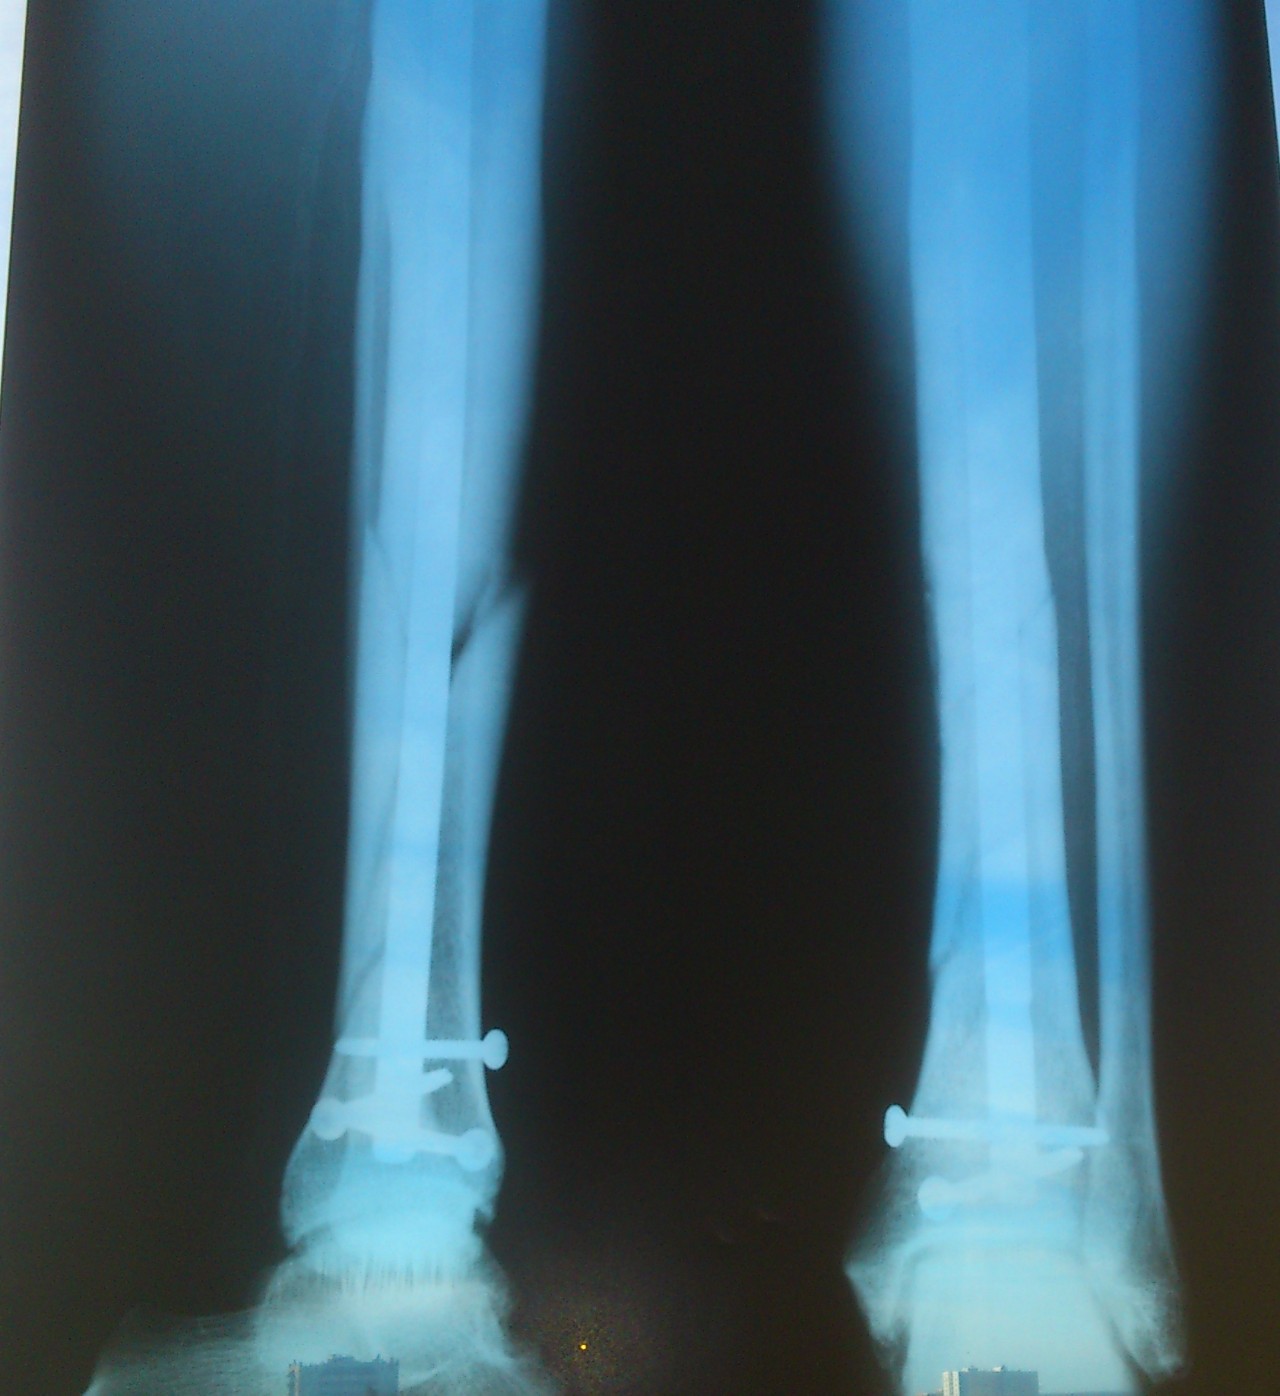

Чрескостный остеосинтез лодыжки

Здесь представлены медицинские изображения переломов большой берцовой кости, сделанные врачами в процессе диагностики и лечения. Вы сможете увидеть, как выглядит этот тип травмы на рентгеновских снимках и других медицинских изображениях.